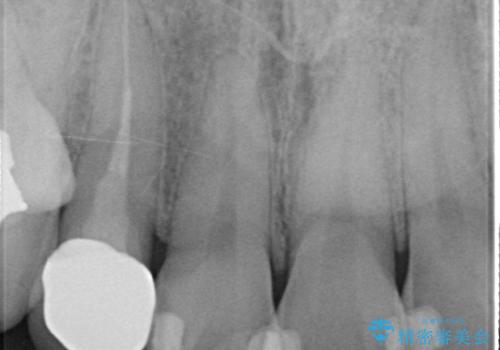

- 右上2番目の歯の被せ物と歯茎の間の継ぎ目が気になるといらっしゃった方の症例です。

再根管治療は希望されなかったため、クラウン除去後、オールセラミッククラウン(スペシャル)による補綴を行いました。

- オールセラミッククラウン(スペシャル)…¥130,000、仮歯…¥10,000、ファイバーコア…¥20,000費用は治療当時の料金となります